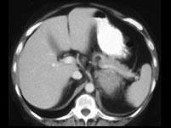

- 单项选择题女,47岁, 满月脸、向心性肥胖伴高血压1月,结合图像, 最可能的诊断是 ( )

A、左肾上腺腺瘤

B、左肾上腺腺癌

C、左肾上腺转移癌

D、左肾上腺嗜铬细胞瘤

E、左肾上腺增生